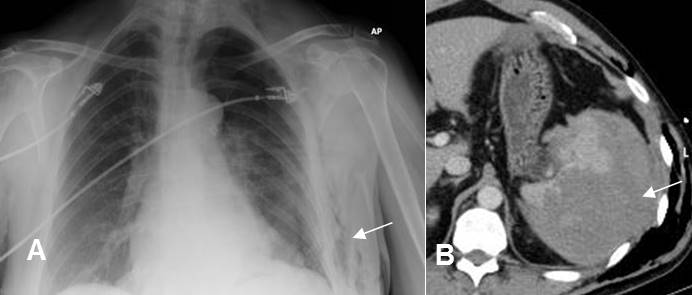

Fig 148. Lesión de vísceras.

A: Rx PA. Enfisema celular subcutáneo, lo que hace sospechar fractura costal y neumotórax.

B: TAC axial. Fractura costal que ocasiona estallido esplénico.